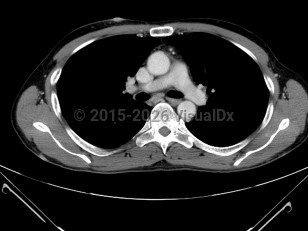

PEL involves serosal surfaces of the body cavities, which include the pleura (60%-90%), pericardium (30%), peritoneum (30%-60%), and joint spaces. Thus it is also known as body cavity lymphoma. Clinical manifestations depend on the extent of serous effusions within those closed serosal surfaces, but there is no lymphomatous mass formation within those cavities. Patients usually present with dyspnea, chest pressure (secondary to pleural or pericardial effusion), abdominal distension and discomfort (due to ascites), or joint swelling.